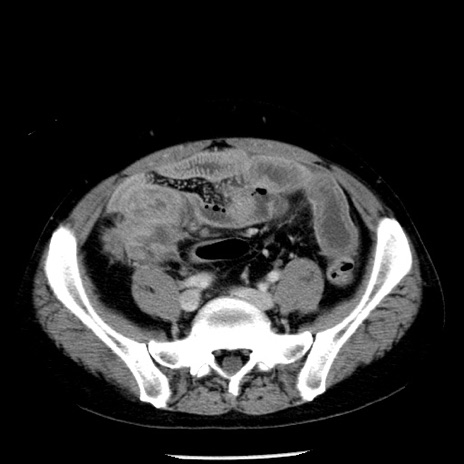

症例29(横断像)

【症例】40歳代男性

【現病歴】2日前から胃痛あり。徐々に周期的な激痛に変化した。本日になっても激痛があるため受診。

【身体所見】意識清明、BT 38-39℃台あり、腹部:膨満、やや硬、右下腹部に圧痛あり。

【データ】WBC 8500、CRP 23.26